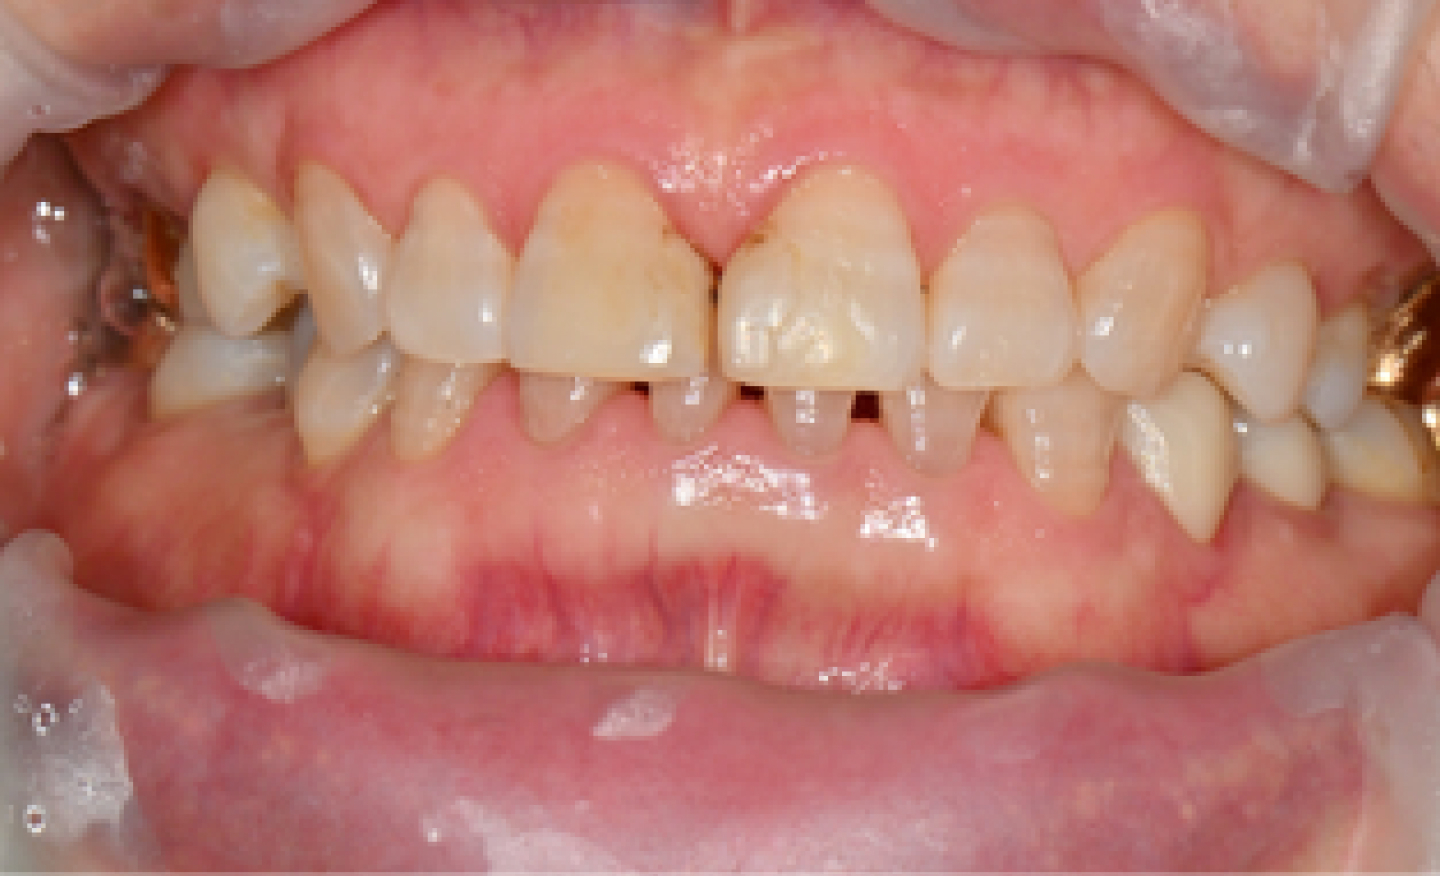

시흥치과 서울안심 앞니 공간 레진치료 시술 전

BEFORE

CASE.

앞니 공간 레진치료

*위의 이미지는 동일한 조건에서 촬영되었으며 별도의 보정 작업을 거치지 않았습니다.

*모든 치료과정에서 부작용이 발생할 수 있으므로 정확한 진단과 수술이 요구됩니다.